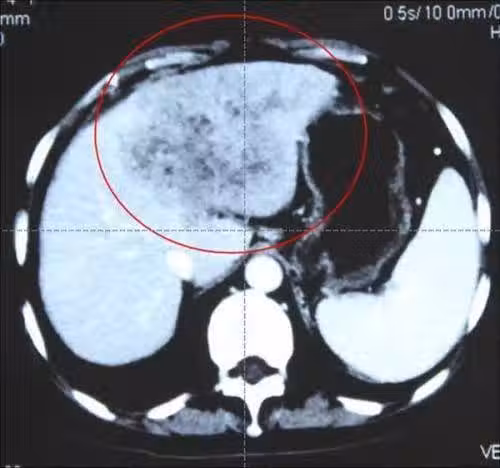

於是小強一次就泡上一盆,放在冰箱裡,下了班抓一把調一下,就著白酒,吃點海鮮。 最近一段時間,小強常常感到右腹部疼痛,同時還伴有腹瀉,臉色是一天不如一天。 於是小強便來到醫院檢查,結果讓他怎麼也沒有想到,竟是查出肝癌ai期,由於並且嚴重,治療5個月後不幸離世。